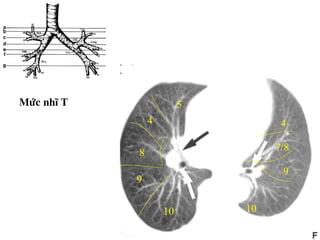

Möùc nhó T

10

5

4

8

9

7/8

TOÙM LAÏI

• Ngang möùc carina: thaáy ñoäng maïch phoåi (T), thaáy

pheá quaûn (P) chia cho thuøy treân baét ñaàu thaáy

phaân thuøy 6 (P).

• Ngang möùc ñoäng maïch phoåi (P): thaáy pheá quaûn (T)

chiaheát thuøy treân xuaát hieän thuøy giöõa, thuøy

löôõi.

• Ngang möùc nhó (T): pheá quaûn (P) chia thuøy giöõa-

döôùi heát phaân thuøy 6 phaân thuøy 8,9,10.

• Ngang möùc 4 buoàng heát haï phaân thuøy 4 (T).